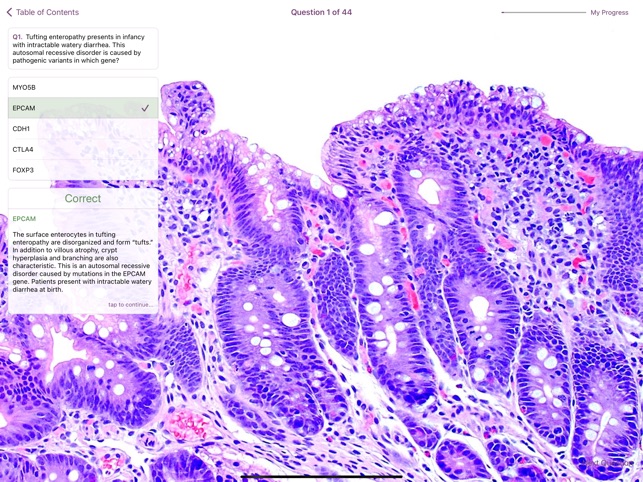

This digital reference atlas from The Johns Hopkins University Department of Pathology is designed for pathology trainees and practitioners. The platform presents a comprehensive collection of over 300 high-resolution images of both common and rare small intestinal entities. It integrates a searchable image database, viewable by diagnosis or feature, with interactive learning modules including image-based quizzes and flashcards. The interface facilitates self-study and aims to support diagnostic confidence in small bowel pathology.